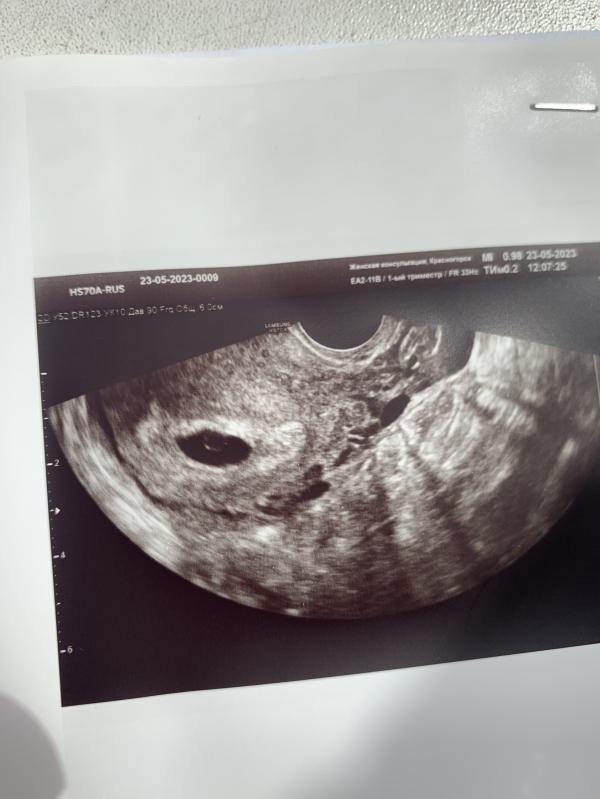

По узи срок 4,6 по месячным 7,6🥺Шла с надеждой увидеть эмбриончика и услышать сердечко, а в итоге одно плодное яйцо и все 😕Перезаписали на 31 мая.

У вас еще желточный мешочек виден ☺ это хорошо) я бы не ходила 31 числа. Вытерпела бы и пошла бы позже. Догонит свой срок. У сеня в этот раз тоже не совпадало по узи и по последним М. Пошла на узи, а там просто плодное яйцо, даже ж/м не было как у вас вон. И потом я выждала 14 дней. Думала сойду с ума. Но в итоге все увидели. Поздняя О была. Расхождение в 5 дней все равно. Но это и по хгч видно было и по тестам.

Тоже так же было 15 го мая ходила только плодное яйцо было. Сходила 22 го уже был виден эмбрион и билось сердечко ☺не переживайте☺